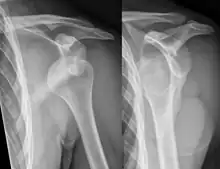

Anterior dislocation of the right shoulder. AP X ray

Anterior dislocation of the right shoulder. Y view X ray.